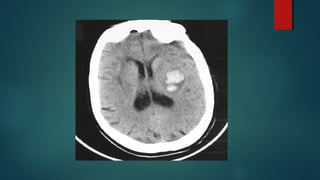

Este documento es el programa para un taller de imágenes del curso de emergencia 2015 impartido por el Dr. Víctor Delgado. El taller se centra en el uso de imágenes médicas para el diagnóstico y tratamiento de pacientes en coma traumático según la base de datos de Marshall. El Dr. Delgado es el único instructor repetido a lo largo del documento.